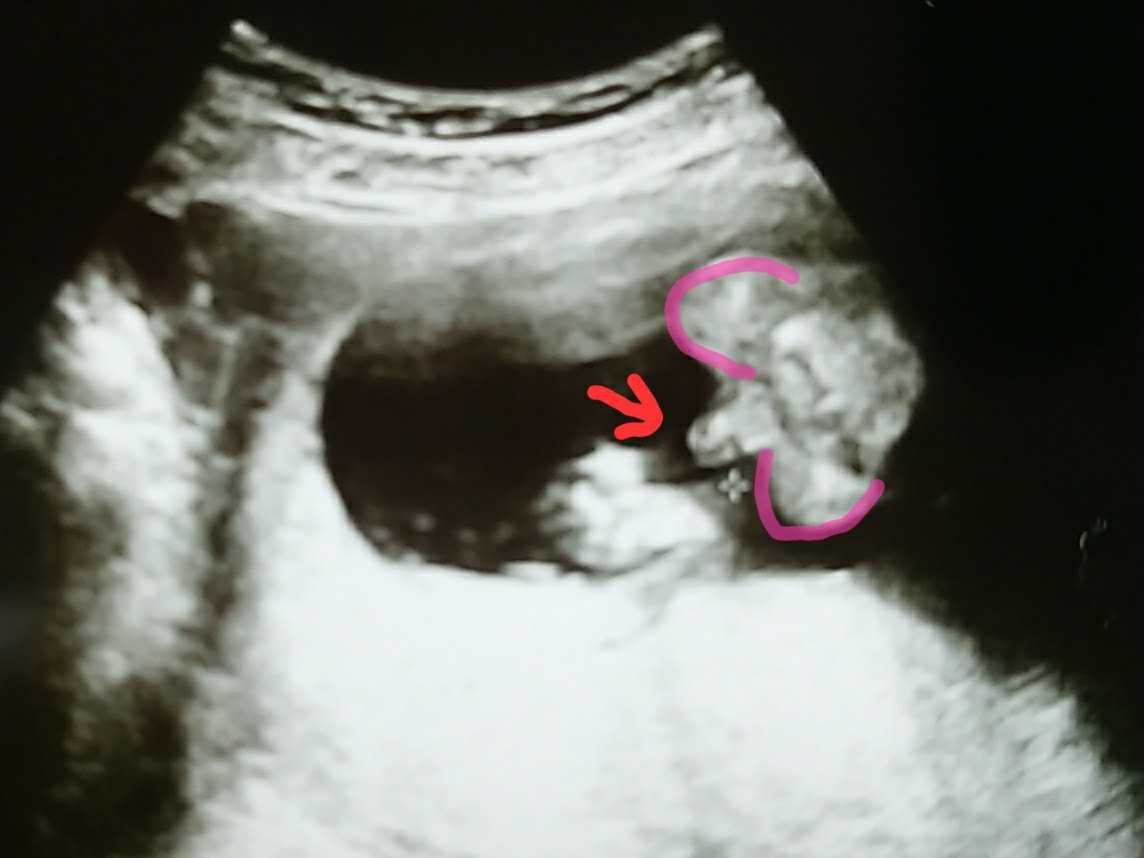

妊娠19週0日(19w0d)ごろの赤ちゃんのエコー写真です。投稿も募集しています。 性別は「女の子」※上の写真がお股を下から撮影したものです。 頭部がピンポン球大、体重は280gでした。お腹の子が「男の子」なのか「女の子」なのか、とっても気になりますよね。 我が家の場合、19週目で股のエコー写真をもらえ、r先生にも男の子だと確定していただきました。 本記事では ベビーナブについて 男の子の11~12週のエコー写真 男の子妊娠18週のエコーで私たちの赤ちゃんは女の子だということがわかりました その鮮明なエコー写真を見てあこれが女の子なんだと納得 多くのエコー検査では99は確実と言われていますがまれに 18 週 女の子 エコー 18週0日18w0d女の 妊娠15週目になると、超

赤ちゃんの超音波、エコー写真。妊娠週ごとに掲載されているので、あなたのエコー写真と比べてみては? 2d、3d、カラー超音波など種類もさまざまですね。(エコー写真の保存) 妊娠中のエコー写真 見たい妊娠月にジャンプ↓23週0日(23w0d・女の子)|どすこい23 さん(25歳) エコー写真撮影時のエピソード: 妊娠23週に撮影しました。 つわりがやっと落ち着いてきて、ご飯を食べるのがおいしくなってきて、赤ちゃんを迎えるためのお部屋の準備を始めました。週数別女の子のエコー写真 ということで過信はしないにせよ、早速他の方のエコー写真を見てみましょう! 妊娠16週目の女の子のエコー写真 16週の早期にはっきりと見えた、希少な例です!

妊娠 16週 エコー写真 先生には女の子と言われた 教えて!goo 妊娠16週で性別確定したよ!性別がわかるエコー画像はコチラ 妊娠16週目(16w0d~6d)のエコー写真とエピソード、ついに 写真多数週数別女の子のエコーの見分け方!性別判定男の子のエコー写真の特徴 胎児の両足の間を見てください。男の子であれば股の間に突起物が確認できるため、女の子よりも早い段階で「男の子」だと判断できることが多いです。 女の子のエコー写真の特徴 女の子の判別する場合も男の子の判別と同様男の子のエコー写真の特徴 胎児の両足の間を見てください。男の子であれば股の間に突起物が確認できるため、女の子よりも早い段階で「男の子」だと判断できることが多いです。 女の子のエコー写真の特徴 女の子の判別する場合も男の子の判別と同様